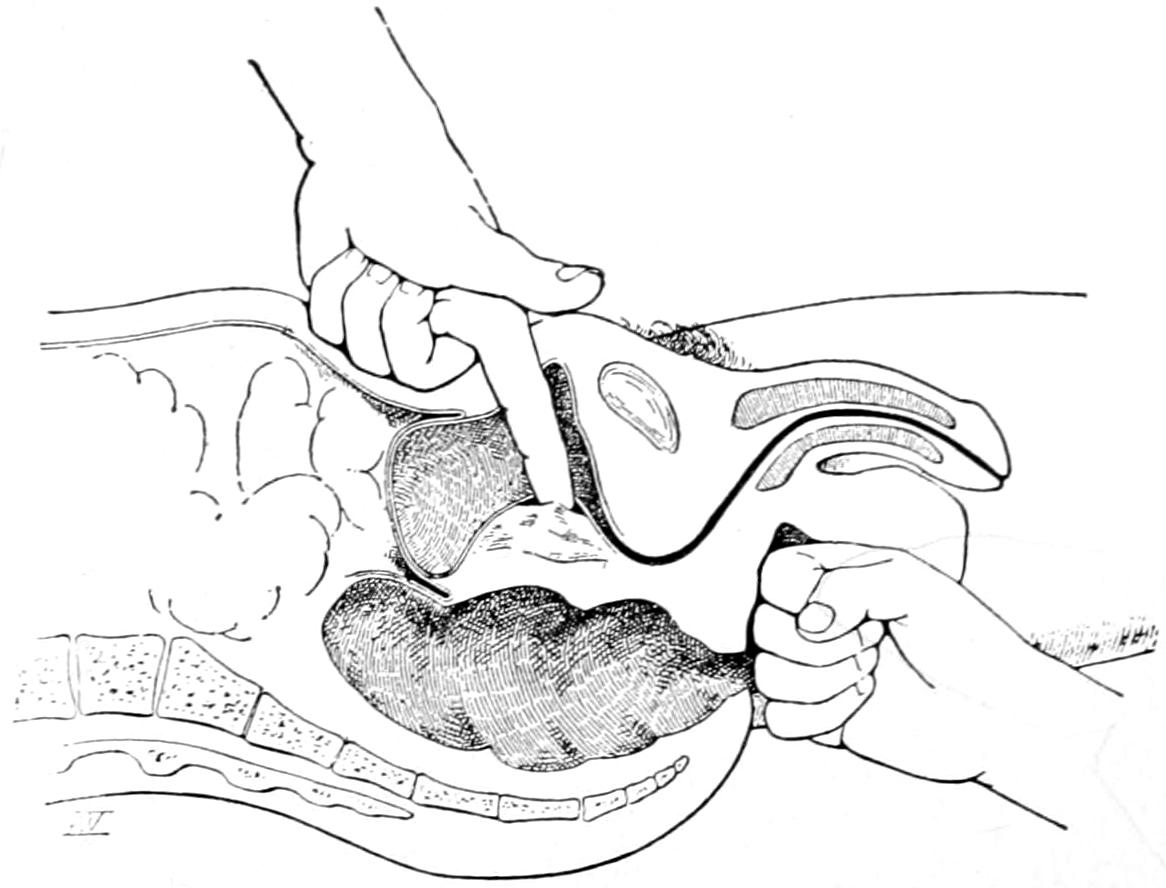

Fig. 1

Congenital hypertrophy: gigantism of both lower extremities. (Case of Dr. Graefe [Sandusky].)